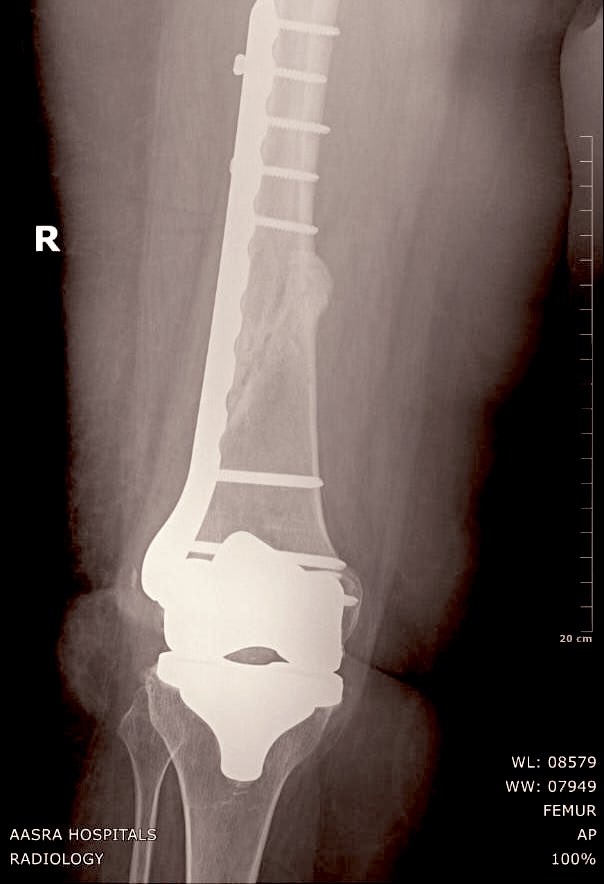

In fifty days this was the status. We allowed partial weight bearing but told her not to move around a lot.

Exactly 80 days after her fracture & fixation we took another X Ray.

It showed good recovery, increasing bone density & some micro trabecular patterns.

We allowed full weight bearing & reiterated again to go slow no hurry.